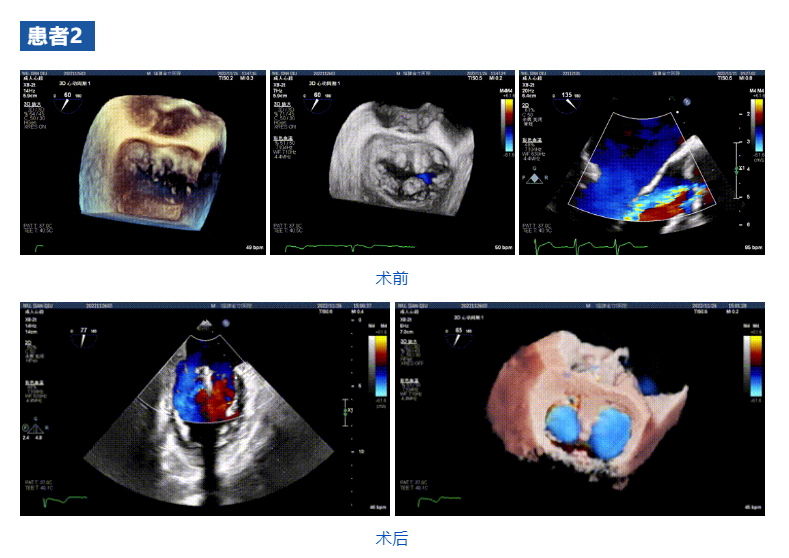

接受治療的三例患者均為器質(zhì)性重度二尖瓣反流(DMR)患者,術(shù)前超聲提示二尖瓣后葉脫垂伴4+反流,左室舒張功能減退。郭延松教授攜同團(tuán)隊(duì)成員陳新敬副教授和洪景宣、方明程、楊清勇主治醫(yī)師、心外科丁杭主任以及超聲科賴(lài)寶春、葉振盛主治醫(yī)師共同進(jìn)行病情討論??紤]到患者高齡、基礎(chǔ)疾病多、STS評(píng)分高,為外科手術(shù)極高危患者,不適合進(jìn)行外科開(kāi)胸二尖瓣手術(shù),因此決定為患者實(shí)施經(jīng)導(dǎo)管緣對(duì)緣修復(fù)介入術(shù)(JensClip經(jīng)導(dǎo)管瓣膜夾系統(tǒng))。

在浙江大學(xué)醫(yī)學(xué)院附屬第二醫(yī)院王建安教授團(tuán)隊(duì)的支持下,手術(shù)經(jīng)股靜脈-房間隔入路,采用全身麻醉插管,在TEE和DSA引導(dǎo)下完成房間隔穿刺。置入JensClip瓣膜夾系統(tǒng)后,在左房調(diào)整瓣膜夾的位置和軸向,后進(jìn)入左室,在TEE引導(dǎo)下捕捉二尖瓣前后瓣葉,并關(guān)閉瓣膜夾。經(jīng)TEE反復(fù)確認(rèn)手術(shù)效果后最終鎖定并釋放瓣膜夾。術(shù)后即刻超聲顯示瓣膜夾位置穩(wěn)定,功能良好,二尖瓣反流由術(shù)前4+減少至微量,手術(shù)圓滿成功。